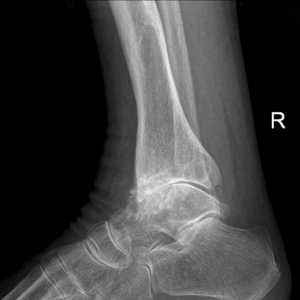

La demanda correspondió por reparto al Juzgado de lo Social n° 1 de Palencia . Tras la admisión a trámite de la demanda señalaron día para el juicio. Nuestro principal objetivo en juicio era hacer entender al Magistrado que el desarrollo de las principales tareas de la profesión nuestro cliente eran incompatible con las ARTRITIS PSORIÁSICA que padece.

Tras la exposición de nuestro abogado el juez decidió a nuestro favor, teniendo en cuenta todos y cada uno de los informes de traumatología, públicos y privados, que aportamos a juicio; avalados por un INFORME PERICIAL de un reputado médico traumatólogo con años de experiencia en la defensa de sus informes en sede judicial.

La ARTRITIS PSORIÁSICA es una enfermedad crónica y progresiva que combina síntomas de artritis con la condición cutánea conocida como psoriasis. Se caracteriza por la inflamación de las articulaciones, que puede llevar a dolor, rigidez y disminución de la movilidad. Además, puede afectar otras partes del cuerpo, incluyendo los tendones y los ligamentos. Según la Fundación Española de Reumatología “la artritis psoriásica, se presenta en aproximadamente entre el 10% y 30% de pacientes que padecen psoriasis en la piel. Puede aparecer antes, a la vez o después que la psoraisis. Incluso existen casos en los que la psoraisis cutánea no aparece en el paciente, pero sí en un familiar de hasta 2º grado. Según datos del estudio de prevalencia de las enfermedades reumáticas en la población adulta española (EPISER 2016), la prevalencia de esta enfermedad es del 0,58%”.